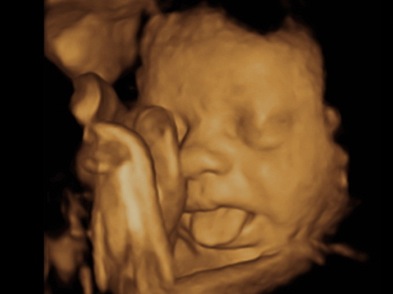

Baby S First Image Las Vegas 3d Ultrasounds During Pregnancy

3d Scanner Image 3d Sonogram